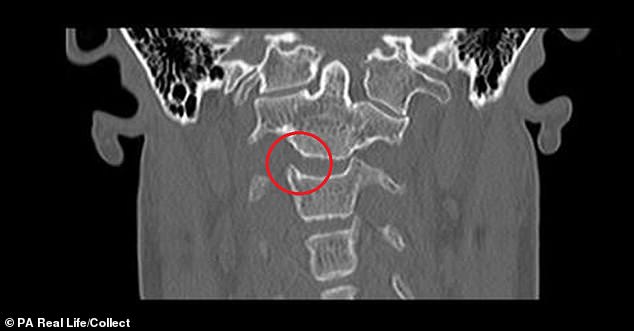

Ảnh chụp chính diện vị trí xương đốt đội trục của Rachel

Các bác sĩ cho biết cô Rachel Pighills mắc chứng mất ổn định đốt đội trục cổ, biểu hiện ở việc di chuyển quá mức của đốt sống thứ nhất và đốt sống thứ hai.

Điều này khiến cột sống của người phụ nữ 33 tuổi dễ dàng bị trật khớp mỗi khi cô quay đầu sang trái và có thể dẫn đến nguy cơ bị tê liệt.

“Tôi đã nói chuyện với một chuyên gia tại Barcelona, ông ấy nói rằng trường hợp của tôi rất nghiêm trọng và tôi có nguy cơ gẫy cổ bên trong”, Pighills kể lại. “Quay đầu sang bên trái có thể khiến khớp sống cổ của tôi bị trật một phần và tôi có thể chết ngay lập tức nếu nó bị trật khớp hoàn toàn”.